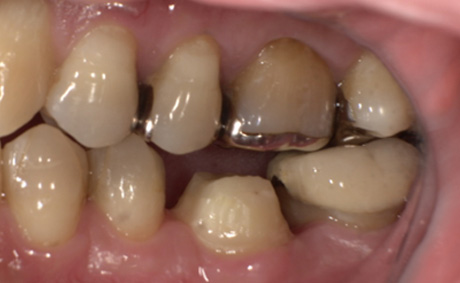

術前・術後の比較

| 術前 | 術後 |

|---|---|

![]() |